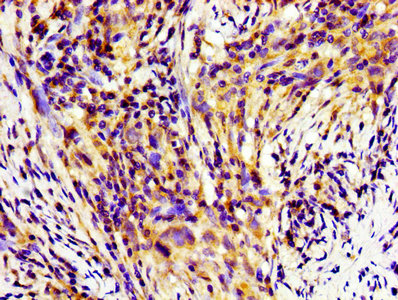

Immunohistochemistry of paraffin-embedded human pancreatic cancer using CSB-PA05639A0Rb at dilution of 1:100